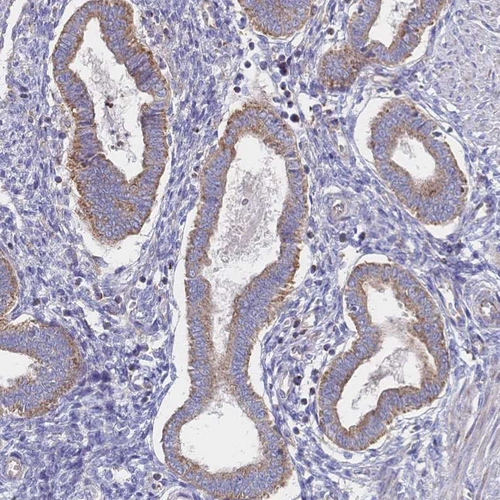

Immunohistochemical staining of human endometrium, gastrointestinal, heart muscle and testis using Anti-SORBS1 antibody HPA043084 (A) shows similar protein distribution across tissues to independent antibody HPA027559 (B).